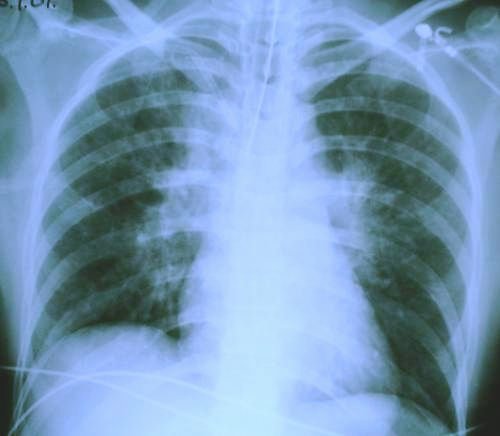

.. and a chest x-ray taken several hours later..

subsequent chest x-ray

The question is, what caused the bilateral pulmonary infiltrates that blossomed in her lungs?

There are several possibilities, but by far the most likely is negative pressure pulmonary oedema . This is a complex phenomenon, related to airway obstruction (or, some allege, to relief of airway obstruction). The likely mechanism is thought to be a compound of massively negative intrathoracic pressure, increased left ventricular afterload, and massive sympathetic outflow, all resulting in pooling of blood in the pulmonary capillaries causing pulmonary oedema.

The woman made a good recovery after 48 hours of ventilation with a positive end-expiratory pressure of 10 cmH 2 and avoidance of diuretic therapy.